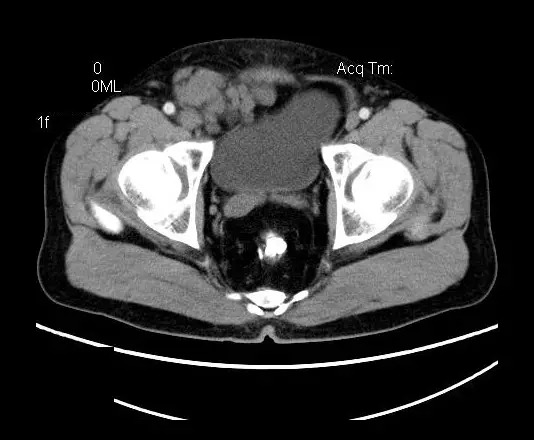

【影像表现】

盆腔右前侧及邻近腹股沟区可见多发大小不等的聚集生长的结节影,病灶呈软组织密度,边缘尚规整,分界尚清,增强扫描可见不均匀强化。膀胱局部受压,盆腔未见明显肿大淋巴结影。

盆腔神经鞘瘤的影像学表现主要取决于肿瘤本身细胞不同组成分布及排列(Antoni A区与B区不同比例)及肿瘤是否发生退变所致。Antoni A 区由密集的梭行细胞构成,细胞核排列为栅栏状或漩涡状。Antoni B区瘤细胞稀疏,网状排列,基质含水量高,常发生囊变或出血。

平扫影像表现:Antoni A区较多病灶,在CT上呈等或略高密度影,T1WI等信号、T2WI略高信号,AntoniB区较多病灶,CT多为水样低密度、T1WI低信号、T2WI明显高信号。

增强影像表现:神经鞘膜肿瘤增强后,由于Antoni A区与B区以不同比例混合而强化不一,呈不均匀斑片状,条状强化。Antoni A 区富血供,中等或明显强化,Antoni B区乏血供,强化多不明显。